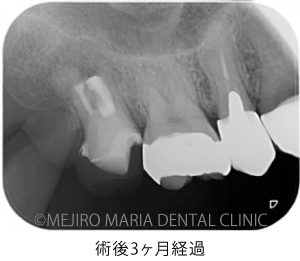

上記のエックス線写真で、術直後に根尖付近に見られた透過像(黒く見える部分)は、3ヶ月後には小さくなり、治癒傾向にあることが確認できます。また、術前に見られた歯周ポケットの改善と瘻孔(フィステル)の消失も確認できます。

歯質が少ない状態ではありますが、術後3ヶ月経過した時点で違和感の消失、病的な歯周ポケットの改善、瘻孔(フィステル)の消失が確認でき、経過は良好です。最終補綴(被せもの)へ移行後も、最低2年間は年1回ほどの経過観察を予定しています。